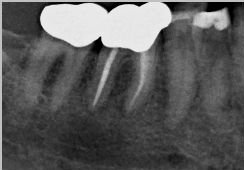

Здравствуйте! Есть ли у меня киста? Если да, то как срочно нужно делать операцию и как она называется?

Какой зуб вы имеете ввиду? Уточните. 18 и 48 зуб необходимо удалить. Далее расскажу после уточнения.